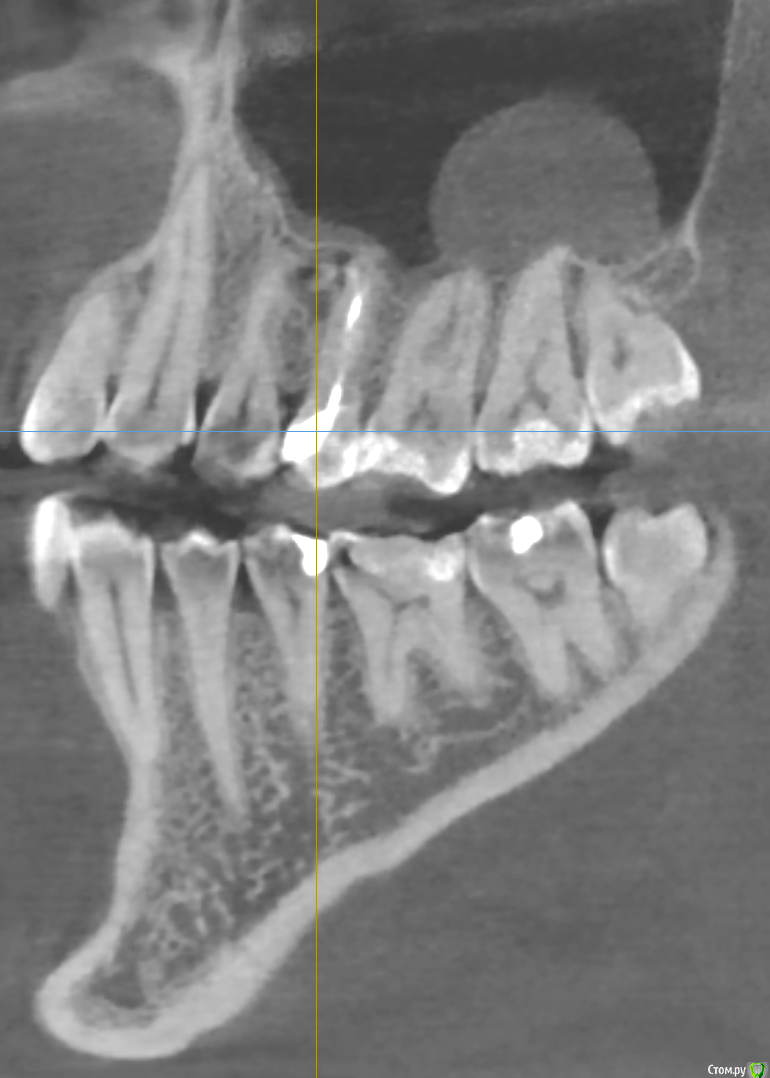

Bier Опубликовано 23 марта, 2018 Поделиться Опубликовано 23 марта, 2018 Если зубы витальные, то подобные образования в лечении не нуждаются. Определите живые ли зубы особенно 7й. Если да, то живите себе спокойно, если нет, то нужно пролечить каналы. У вас есть какая то проблема в области 4-5 зубов, срез КТ стоит нечетко и подробнее не ответить. Ссылка на комментарий

tmporaries Опубликовано 23 марта, 2018 Автор Поделиться Опубликовано 23 марта, 2018 Спасибо за ответы.Киста никак не беспокоит, обнаружили её случайно на КТ.5-ый зуб сверху был перелечен год назад. Ссылка на комментарий